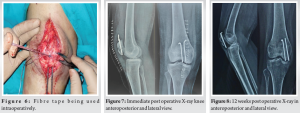

The patella serves as a pivotal component in the biomechanical function of the knee extensor apparatus [1]. Fractures of the patella have the potential to disrupt this mechanism, particularly when combined with incongruent posterior articular surfaces, leading to persistent issues like discomfort arising from femoropatellar arthritis [2,3]. Patellar fractures commonly stem from two primary mechanisms: Direct impact on the anterior knee or indirect injury resulting from eccentric contraction of the quadriceps muscle [4]. Surgical intervention becomes necessary in about one-third of patients affected by these fractures. Tension band wiring using stainless-steel wires has long been considered the gold standard for surgically managing displaced patellar fractures (Fig. 1 and 2) This technique effectively converts tension from muscle pull into compression at the fracture’s articular side, promoting improved fracture union by providing absolute stability through interfragmentary compression in bending fractures. However, its widespread use has been subject to debate due to the high incidence of resurgery rates attributed to issues such as implant impingement, skin infection, and wire breakage [5,6] (Fig. 3 and 4). Also for multifragmented stellate fracture, where encircle is required, SS wires require multiple passes through retinaculum with 4-mm-thick wire passer which is more traumatic. An alternative to traditional metal wire for patellar fracture fixation is non-absorbable suture, such as fiber tape (Fig. 5), which has been shown to yield similar outcomes with a reduced complication rate and comparable strength in biomechanical studies. Multiple passes in encirclage method for comminuted fractures with fiber tape is less traumatic with 2-mm needle. Research conducted by Arthrex found that fibreTape exhibited significant strength at 3 mm elongation and shows good loop integrity [7].

Following the surgical procedure, the knee is secured in a long knee brace for 4 weeks, with suture removal scheduled at 14 days. Partial weight bearing with assistance is permitted after 2 weeks. Subsequent check-ups occur at 3-week and 6-week post-surgery. At 4 weeks, range of motion exercises is commenced with a focus on restoring active knee flexion. Rehabilitation progresses with active flexion movements at 5 weeks, culminating in the conclusion of care at 12-week post-surgery (Fig. 8-10).